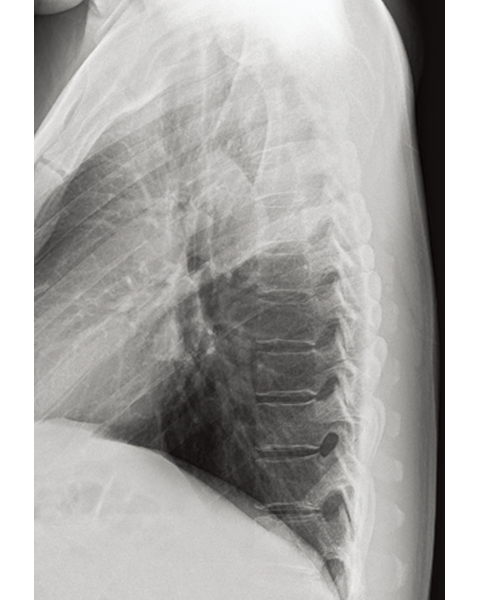

Virtual Grid

Provides a high quality image without using a grid

Virtual Grid processing corrects for the effects of scatter radiation. Without the need for a grid, Virtual Grid retains high contrast and image sharpness, while preventing the asymmetric density  resulting from misalignment of X-ray tube and detector. (Option)

Virtual Grid​

No Grid

Real Grid